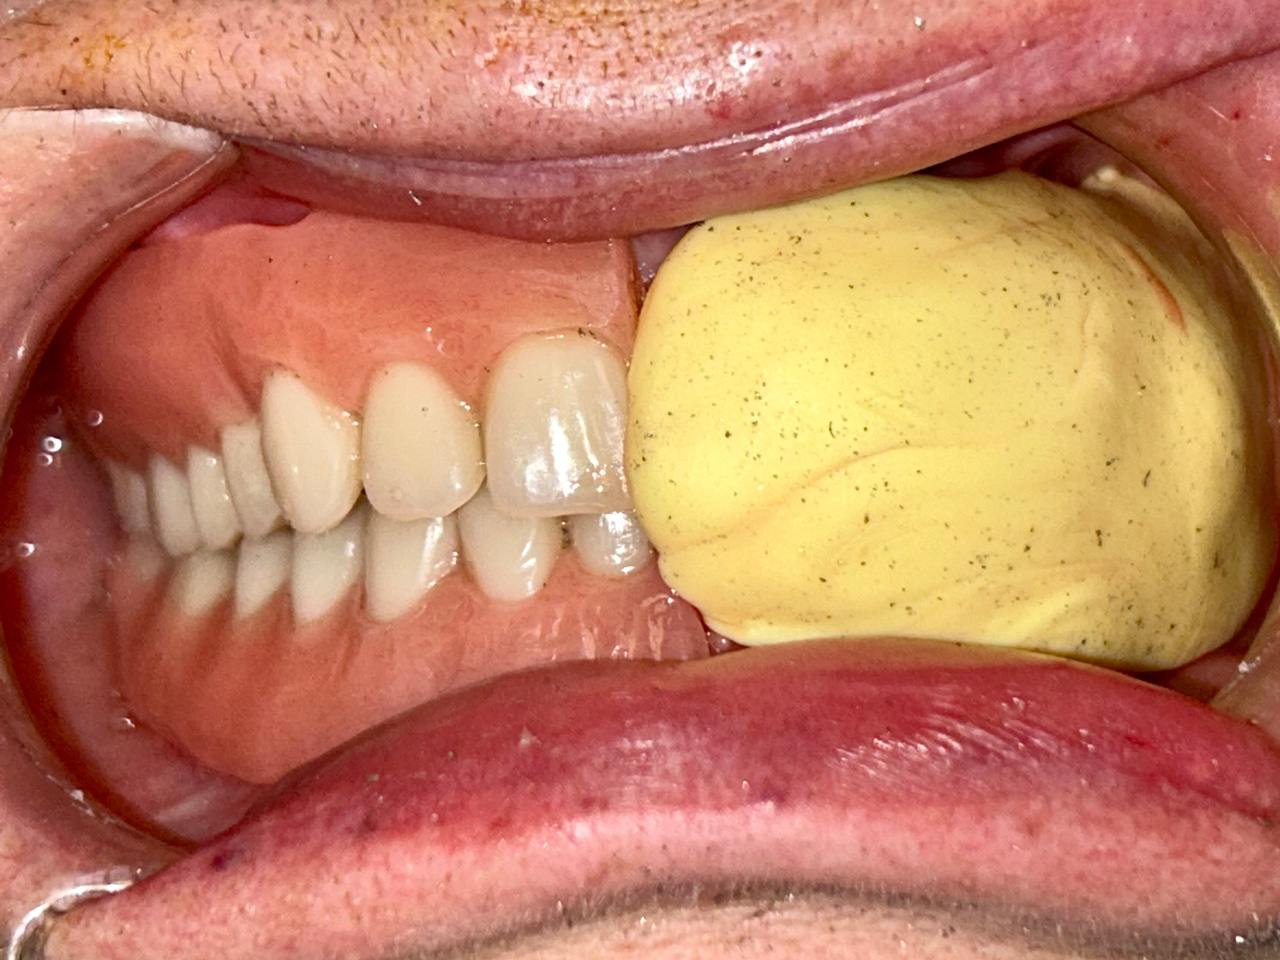

Teljes szájüregi rehabilitáció két lépésben

Ismét egy teljes szájüregi rehabilitáció két lépésben. Először az alsó fogak lettek kihúzva és azonnal implantálva, híddal ellátva, majd később a felső. IHDE svájci azonnal terhelhető implantátumok és cirkónium hidak. Dr. Kelemen Péter és a Symbion Fogtechnika közös munkája.